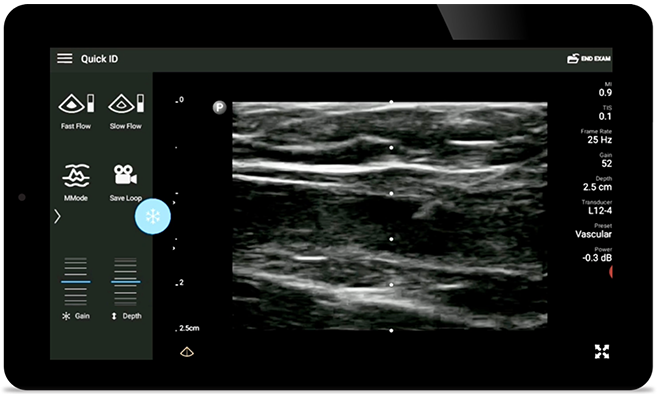

Broadband linear array transducer

Lumify L12-4 broadband linear array transducer

• 12 to 4 MHz extended operating frequency range

• Aperture size: 34mm

• 2D, steerable color Doppler, M-mode, advanced XRES and multivariate harmonic imaging, SonoCT

• High resolution imaging for shallow applications: soft tissue, vascular, superficial, musculoskeletal, and lung

• Center line marker

• USB-C transducer with replaceable cable